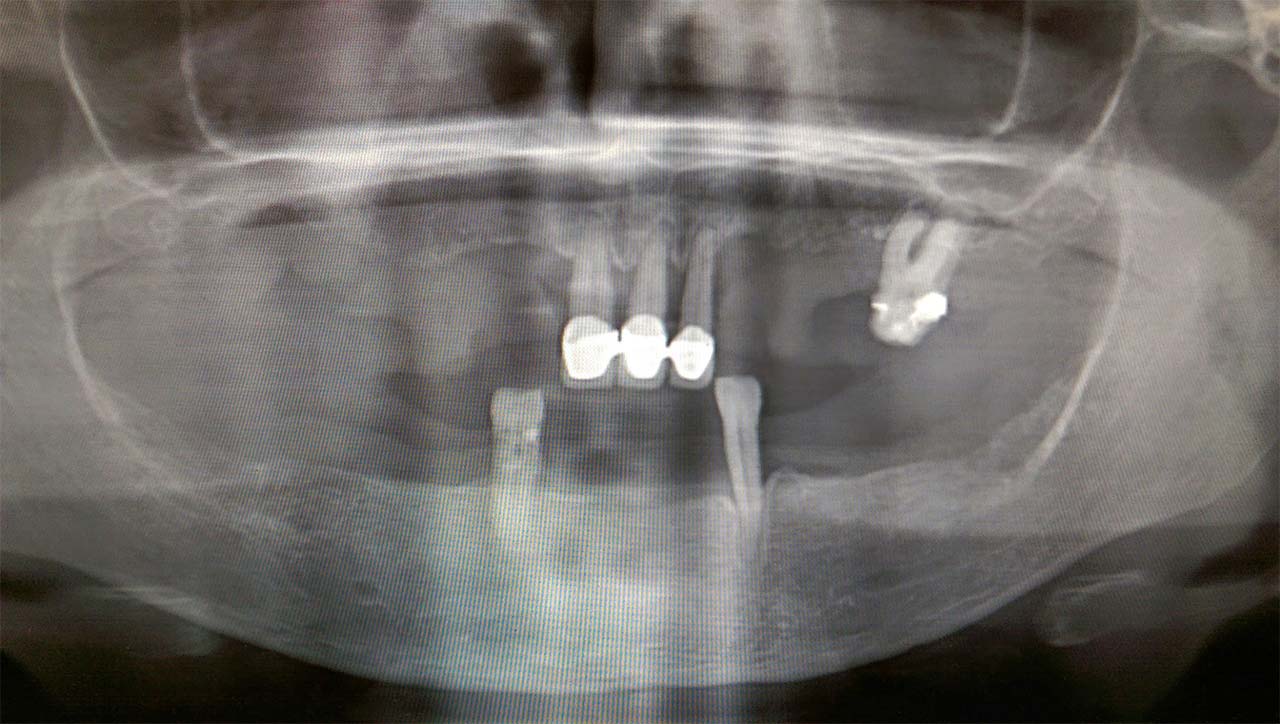

80 év felett is működik!

Teljes alsó, felső állcsont rehabilitáció azonnal terhelhető implantátumokkal és porcelán hidakkal.

Csontritkulás, cukorbetegség, súlyos fogágybetegség és dohányzás nem befolyásolja a sikerességét.